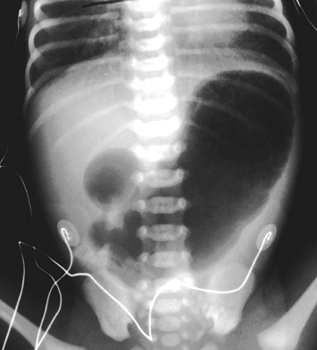

Pediatric Radiology > Abdominal > Neonatal > Duodenal Atresia (2)

Duodenal Atresia - Radiographic Features

The most prominent feature is the "double bubble" sign (dilated stomach and duodenal bulb) -- dilated stomach and no gas distal to the proximal duodenum. Stated another way, there is no gas in the rest of the small or large bowel. |